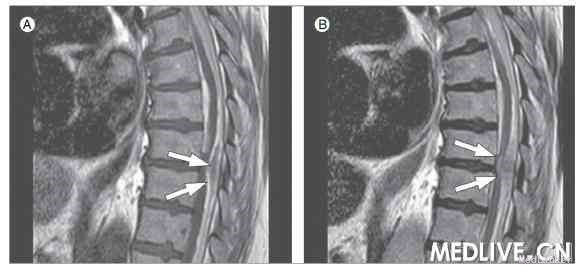

2008年12月,一名70岁的老人来医院就诊,主诉为下背部疼痛向腰部放射,并伴右腿无力。疼痛发生在当天早些时候,当时患者准备乘火车出行。患者一般情况良好,但长期患有高血压,一直在服用普萘洛尔、西拉普利、阿司匹林和阿托伐他汀等药物。全身检查和神经系统查体无明显异常。给予曲马多镇痛。腰部影像学检查显示退行性变、膀胱扩大。白细胞计数为15.9×109/L(中性粒细胞占88%)。患者导尿后有700 ml残余尿,尿沉渣镜检发现少量白细胞。遂诊断为尿路感染,并给予氧氟沙星和阿夫唑嗪治疗。 第2天, 患者于坐位时发生了晕厥, 疑为药物引起的体位性低血压。2 h后, 患者诉自己的右腿已经没有感觉。腿部肌力明显降低( 3~4级) , 巴彬斯基征阳性,且血压升高至204/124 mmHg(1 mmHg ≈0.133kPa)。诊断患者发生了高血压危象和脑血管意外,紧急静脉内给予硝酸酯类药物。头部CT显示双侧枕部有小面积的蛛网膜下腔出血,但在CT血管造影中却未查到引起出血的原因,考虑可能是创伤后的蛛网膜下腔出血。当天夜里患者变得焦躁不安,出现了急性谵妄。测血压为150/100 mmHg,停止给予硝酸酯类药物。随后患者又诉后背部严重的疼痛,持续约90 min。1 h 后,患者出现了呼吸困难且动脉血氧饱和度降低,并呕出大量咖啡样物质,血压骤降至82/56 mmHg。当即予气管插管通气及强心治疗。连续的心电图和血清肌钙蛋白浓度测定未出现变化。血液检查显示白细胞升高和肾前性氮质血症,转氨酶也明显升高。疑有主动脉夹层或内出血。然而血红蛋白浓度维持稳定,且全面的影像学检查也并未显示明显的病理征象。脓毒性休克和能分泌肾上腺素的肿瘤也被排除。之后的24 h患者病情较稳定,撤除了气管插管及强心支持。此时的神经系统查体表现为软瘫,右侧肢体无力更为明显,双侧巴彬斯基征阳性,T2水平感觉减退。科内讨论倾向于遵循“奥卡姆剃刀原则”[1](如无必要,勿增实体),即单一的一体化诊断。脊髓MRI显示T2~L3节段后位的亚急性硬膜下血肿,并伴有脊髓压迫(附图)。对患者紧急行椎板切除术(T9~10)及血肿清除术。2009年3月最后一次复查时,患者正在接受康复治疗,情况逐渐好转但仍需坐轮椅。